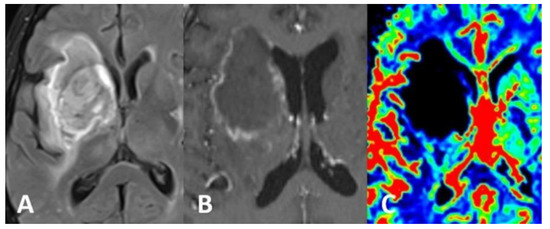

Computed tomography (CT) scan of the brain revealed the presence of a focal space-occupying hypodense lesion in the right basal ganglia, surrounded by edema. The lesion caused mass effect with effacement of ipsilateral cerebral sulci, buckling of the ventricular system (without hydrocephalus) and mild deviation of midline structures to the left (Figure 1). On magnetic resonance imaging (MRI), the lesion was relatively heterogeneous on T2/FLAIR and exhibited marginal enhancement following gadolinium injection. Perfusion-weighted imaging demonstrated significant decrease of cerebral blood flow (CBV) within the lesion (Figure 2). Following imaging characterization of the lesion, an intraoperative consultation with brain biopsy was performed through a right parietal burr hole. A brain smear revealed the presence of brain tissue with abundant dirty necrosis and predominantly acute inflammatory cells. Cystic structures containing encapsulated microorganisms were also identified, raising the hypothesis of TG infection. A brain biopsy was later performed and revealed not only cysts containing bradyzoites but also free microorganisms (tachyzoites) across the sample. Immunohistochemical staining with antibodies against TG confirmed the diagnosis of cerebral toxoplasmosis, highlighting the free tachyzoites (Figure 3). A post-biopsy CT scan excluded procedure-related complications.

Figure 2.

MRI of the brain showed a heterogeneous lesion on the T2/FLAIR sequence (A), displaying ring-enhancement after gadolinium injection (B). Perfusion-weighted imaging showed significant decrease of CBV (C) within the lesion.

The differential diagnosis of cerebral toxoplasmosis is extensive and includes lymphoma, metastasis and other opportunistic infections, as these entities may share similar imaging features [2]. Nonetheless, the presence of a small mural nodule within the ring-enhancing lesion (“eccentric target sign”) and/or the existence of concentric alternating zones of hypo and hyperintensity on MRI (“concentric target sign”) suggest the diagnosis of toxoplasmosis [16]. Moreover, low metabolic activity on thallium single-photon emission computed tomography (SPECT) and/or positron emission tomography (PET) and decreased CBV on perfusion-weighted MRI favor the hypothesis of a pseudotumoral mass (such as infection) instead of a brain tumor or metastasis [2].